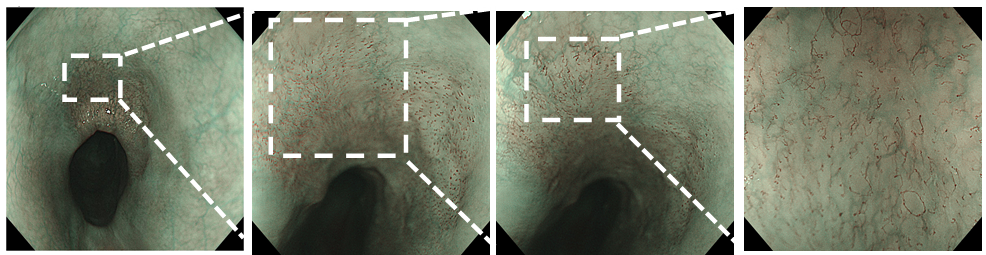

入院后完善胃镜检查:食管距门齿25~30 cm处见一片状黏膜色泽发红,其上血管网透见不良,NBI模式下见茶褐色区域,边界清楚,碘液喷洒后病变区域淡染色,稍吸气可见“榻榻米”征。

逐步放大,此区域IPCL相对比较稀疏,但是可以看到典型的IPCL呈B1改变,形成玫瑰花环样结构。